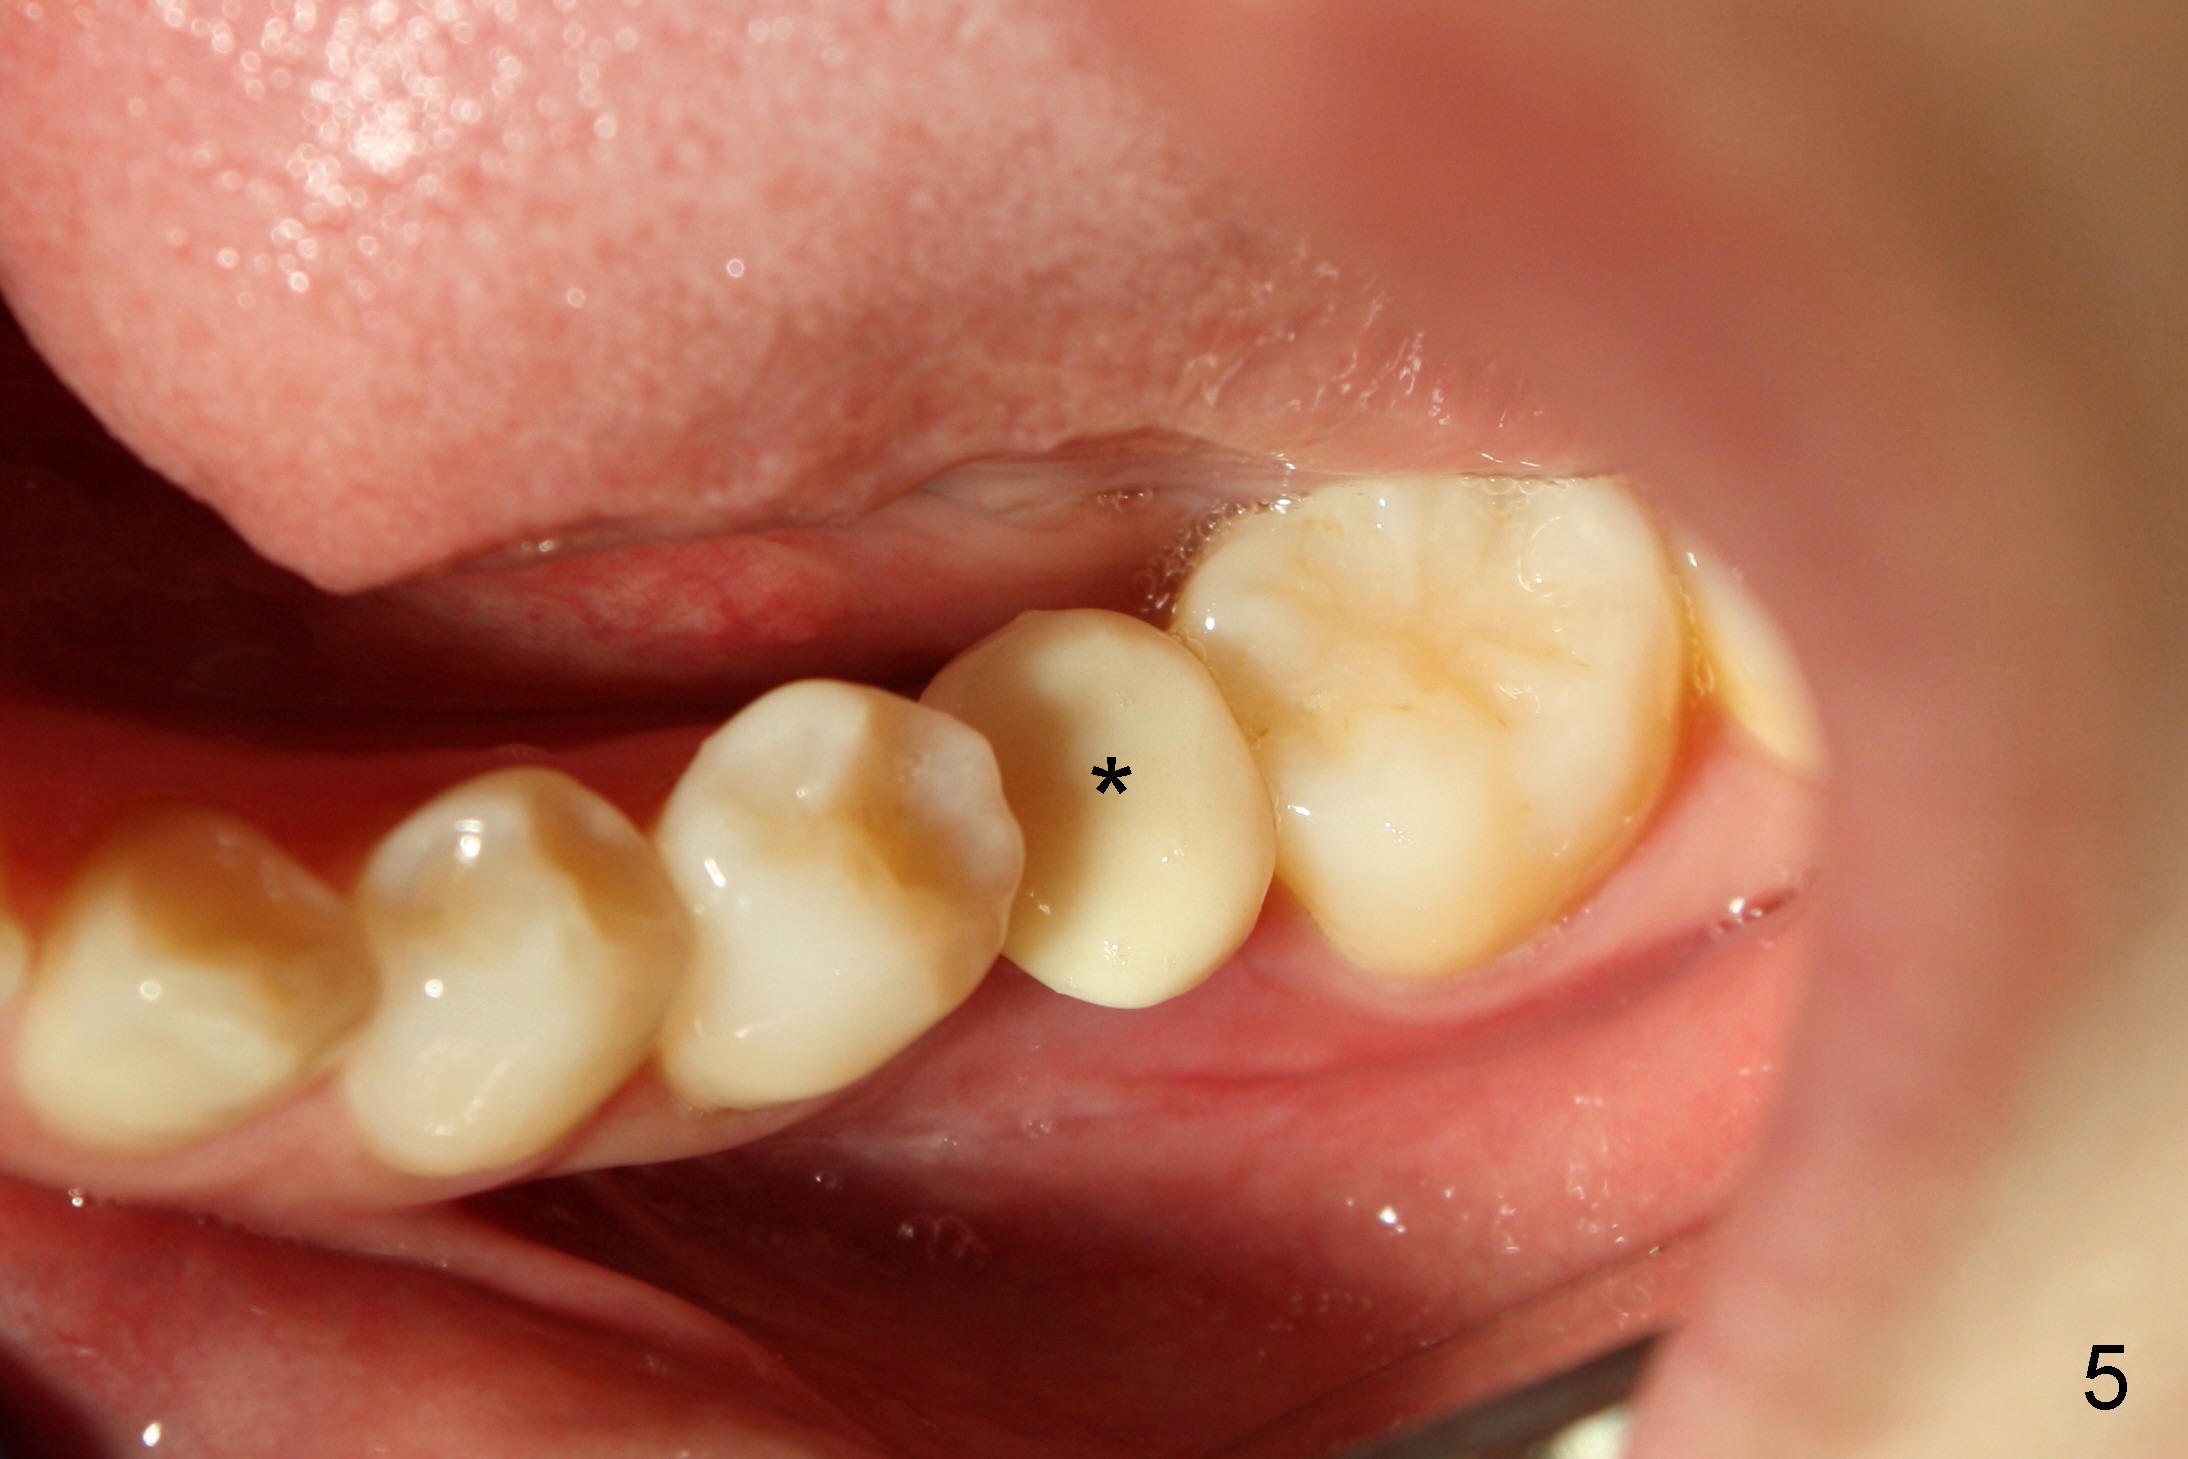

那天我们只做下颌植牙修复,但是困难重重,基牙要磨去很多,对合牙不敢惹:右上处女牙不敢碰,而左上还有牙痛,更不敢动手动脚,所以下颌临时牙冠又小又矮(图五*,左下),看上去真伤心。虽然做两侧取模,但是告诉实验室只作右下陶瓷牙冠(Zirconia, i.e., Bruxir. It is reported that this crown will never break.),左下牙冠等左上根管治疗后一起做,好像挺上策,为自己小聪明沾沾自喜。